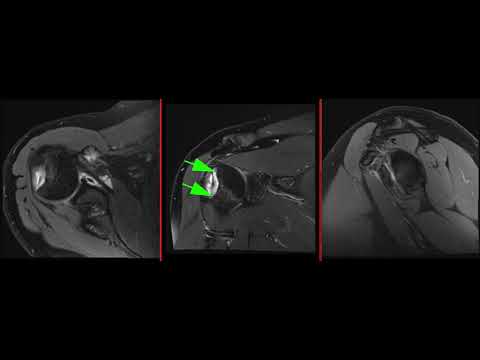

Артроз плечевого сустава 3 стадии, акромиально-ключичный артроз. Подакромиальный импинджмент с полным разрывом сухожилий над- и подостной мышц, частичным повреждением верхних волокон сухожилия подлопаточной мышцы. Атрофия подлопаточной мышцы 2 степени, 3 степени - над- и полостной мышц. Дегенеративные повреждения переднего, переде-верхнего, заднего краев суставной губы. выпот в полости сустава, теносиновиит.